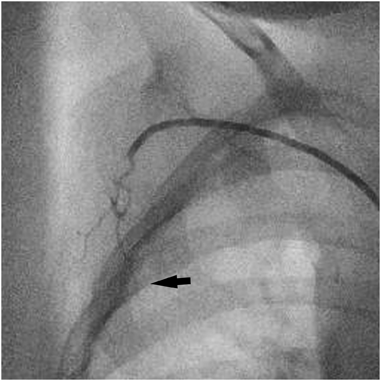

Supplemental Fig. Cardiac catheterization image

A 2-year-old girl, with a history of complete atrioventricular septal defect with hypo LV that was palliated with Glenn procedure, underwent transcatheter coil embolization of minor APCAs before the Fontan operation. Her SpO2 was 75% at room air. About 5 mm length of a minor APCA branching from her right subclavian artery was obtained in the catheter session. Thus, the histology of the specimen was investigated. Interestingly, a cross section of the specimen showed that the single minor APCA was composed of two small arteries, four capillaries, and an unclassified vessel, assessed by hematoxylin-eosin staining and immunohistochemistry using CD31 (vascular endothelial marker), EphB4 (venous endothelial marker), and Ephrin B2 (artery and capillary endothelial marker) antibodies (Fig. 1A–D; Fig. 2A, B). In addition, these vessels were embedded in supporting tissue surrounded by a capsule-like outer-membrane which was positively stained with Ephrin B2 (Fig. 2A, B). These results indicated that several types of vessels branched from a single minor APCA in its peripheral site even though it appeared to be a single vessel lumen on angiography (Fig. 2C).